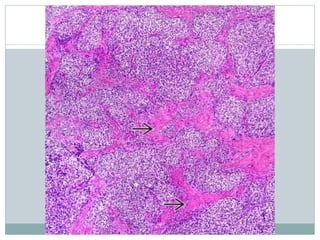

• #13 This case of ES features a more prominent lobulated pattern of growth with large nests and sheets of clear tumor cells separated by thickened fibrocollagenous septa .

• #14 Some cases of ES feature conspicuous morphologic evidence of neuroectodermal differentiation in the form of scattered true rosettes . These tumors have also been described as primitive neuroectodermal tumors (PNETs). The true rosettes of ES (PNET) are formed by tumor cells arranged around a core of fibrillary material without formation of a central lumen. Cell boundaries are indistinct. These structures are also known as Homer Wright rosettes.